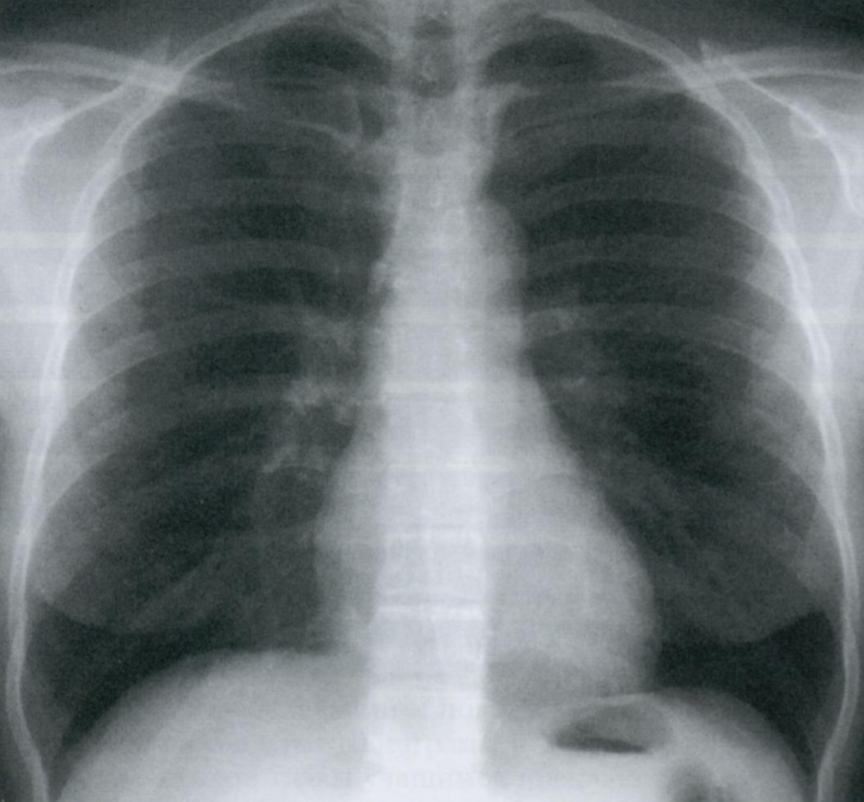

21

Q

Что отмечено стрелками на снимке?

Что такое линии Кёрли? Какие типы Вы знаете?

Интерстициальные заболевания легких характеризуются ретикулоузловой картиной паутиноподобных затенений из-за наложения отечных междольковых перегородок + мелкоочаговых затенений с четкими границами.

A

Поверхностные лимфатические протоки легких, в даном случае с признаками застоя походу междольковых перегородок.

На снимке становятся видны в виде линий, которые мы называем линиями Керли. В даном случае линии Керли типа В (короткие линейные затенения 1-2 см. в сублевральной области (на периферии полей легких) в нижнем или среднем отделе легких.

Линии Керли типа А более длинные (до 5 см.), идут от корней легких в верхней доле.

Есть карточка с делением легких на отделы (отделы - не доли, а как бы три этажа легочного поля, чтобы более понятно описывать локализацию структур именно на снимке).